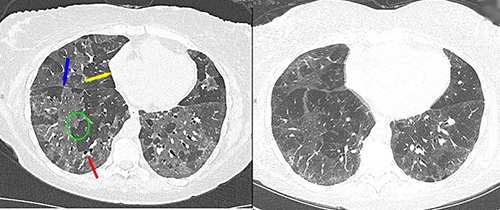

Dr. Hoffman’s research group, the Advanced Pulmonary Physiomic Imaging Laboratory (APPIL), and colleagues have pioneered computed tomographic (CT) imaging methods to study the links between lung structure and lung function.1 In the early 2000s, the group began experimenting with advanced, clinically viable CT protocols that could measure not just anatomy but also physiology—how air moves in and out of tiny peripheral air spaces, how blood flows through the intricate vascular network, and how the delivery of blood (perfusion) and fresh gas (ventilation) is optimized for normal physiologic respiratory processes. By overlaying color-coded maps of perfusion and ventilation on lung images, the APPIL group revealed striking early disease patterns—even in smokers who passed spirometry with normal scores.2 Smokers with only the faintest signs of emphysema on CT images (but demonstrating a susceptibility to emphysema) showed markedly more heterogeneous perfusion than healthy controls. The scans unveiled a new finding—patchy areas of poor blood flow and uneven air distribution that hinted at future disease. The discovery was profound: Vascular dysfunction showing as irregular, fragmented blood flow patterns—long thought to be a late consequence of smoking-related injury—is among the very first changes in the disease process.

Building on these insights, Dr. Hoffman and his colleagues were able to take advantage of advanced dual-source, dual-energy computed tomography (DECT) to measure regional lung ventilation and regional perfused blood volume (PBV; a surrogate for perfusion). This approach considerably simplified the need for dynamic scan sequences used in the earlier studies discussed above. Their DECT-PBV studies showed that after treatment with sildenafil (a vasodilator that inhibits peripheral vascular constriction occurring in response to low oxygen content), abnormal perfusion patterns in smokers with early emphysema became more uniform. This matched the patterns in smokers not shown to be susceptible to emphysema. This demonstrated that the perfusion heterogeneity was not a result of peripheral injury but may in fact be a source of lung injury. This is remarkable, because the technology allows not only visualizing the presence of early disease processes but also its potential reversibility from treatment.